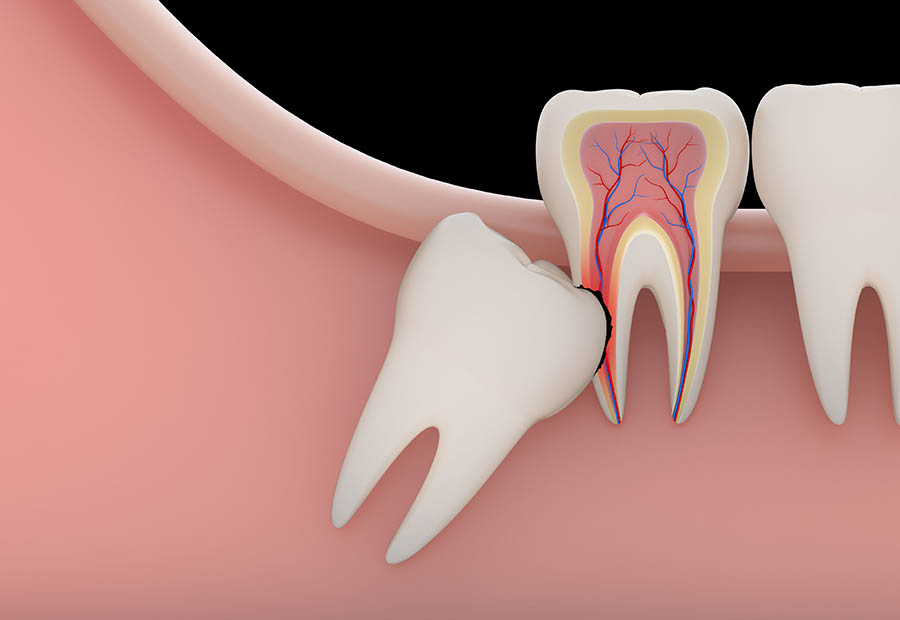

Root Canal Treatment

Root canal treatment is the removal of the tooth's pulp, a small, thread-like tissue.